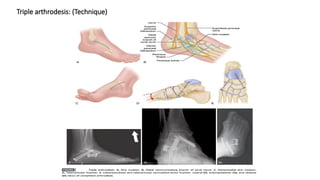

Triple arthrodesis: (Technique)

Few modifications:

(Lambrinudi arthrodesis:)

• For correction of isolated fixed equinus deformity in patients older than 10 years

• Wedge of bone is removed from the plantar distal part of the talus

• The talus remains in complete equinus at the ankle joint while the remainder of the

foot is repositioned to the desired degree of plantarflexion

• Tendon resection or transfer may be necessary to prevent varus or valgus deformity

if active muscle power remains

A, Colored area indicates part of talus to be resected.

B, Sharp distal margin of remaining part of talus has been wedged into

prepared trough in navicular,and, and raw osseous surfaces of talus, calcaneus, and cuboid

have been apposed.

LAMBRINUDI